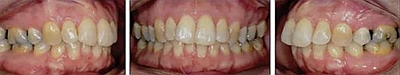

患者曾行正畸治療,現覺笑容不美觀前來就診?;颊哒嬗^及側貌示下頜發(fā)育不足,偏高角,唇閉合不全。上下頜中線齊。覆合、覆蓋4毫米。磨牙關系及尖牙關系II類。上頜擁擠度4mm,下頜擁擠度6mm。4顆第一前磨牙在第一次正畸治療時已拔除。上下牙弓呈尖圓型,牙弓狹窄。

患者側貌改善,下唇唇肌緊張消失,上下唇可自然閉合。磨牙及尖牙關系糾正至I類,覆合覆蓋正常。上下頜弓型糾正至卵圓形,牙弓寬度增加。頭影測量分析示SNA角81.8°,ANB角3°。頭影測量重疊圖示下頜骨向后旋轉,垂直面高度略有增加。